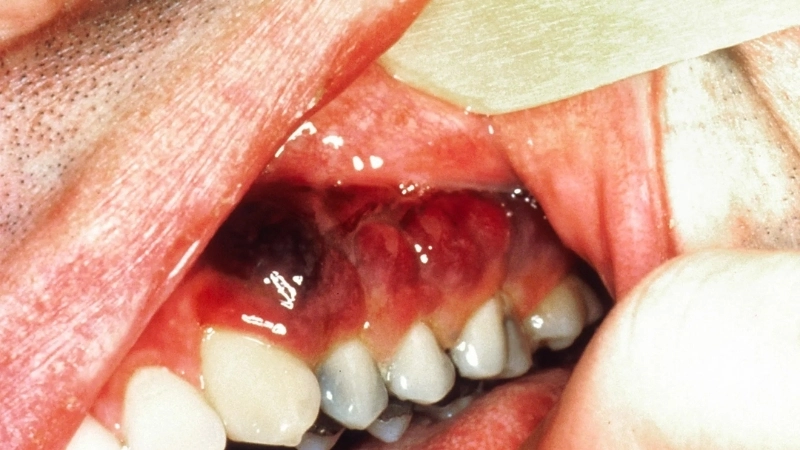

Image description of Kaposi's Sarcoma

Kaposi's Sarcoma is a rare cancer caused by human herpesvirus 8, primarily affecting skin, lymph nodes, and internal organs. It often presents as purplish lesions or swelling and is more common in individuals with weakened immune systems.

Kaposi's Sarcoma shows skin lesions

• Purplish, red, or brown patches on the skin are the most common visible symptom of Kaposi's Sarcoma, often appearing on the legs or face.